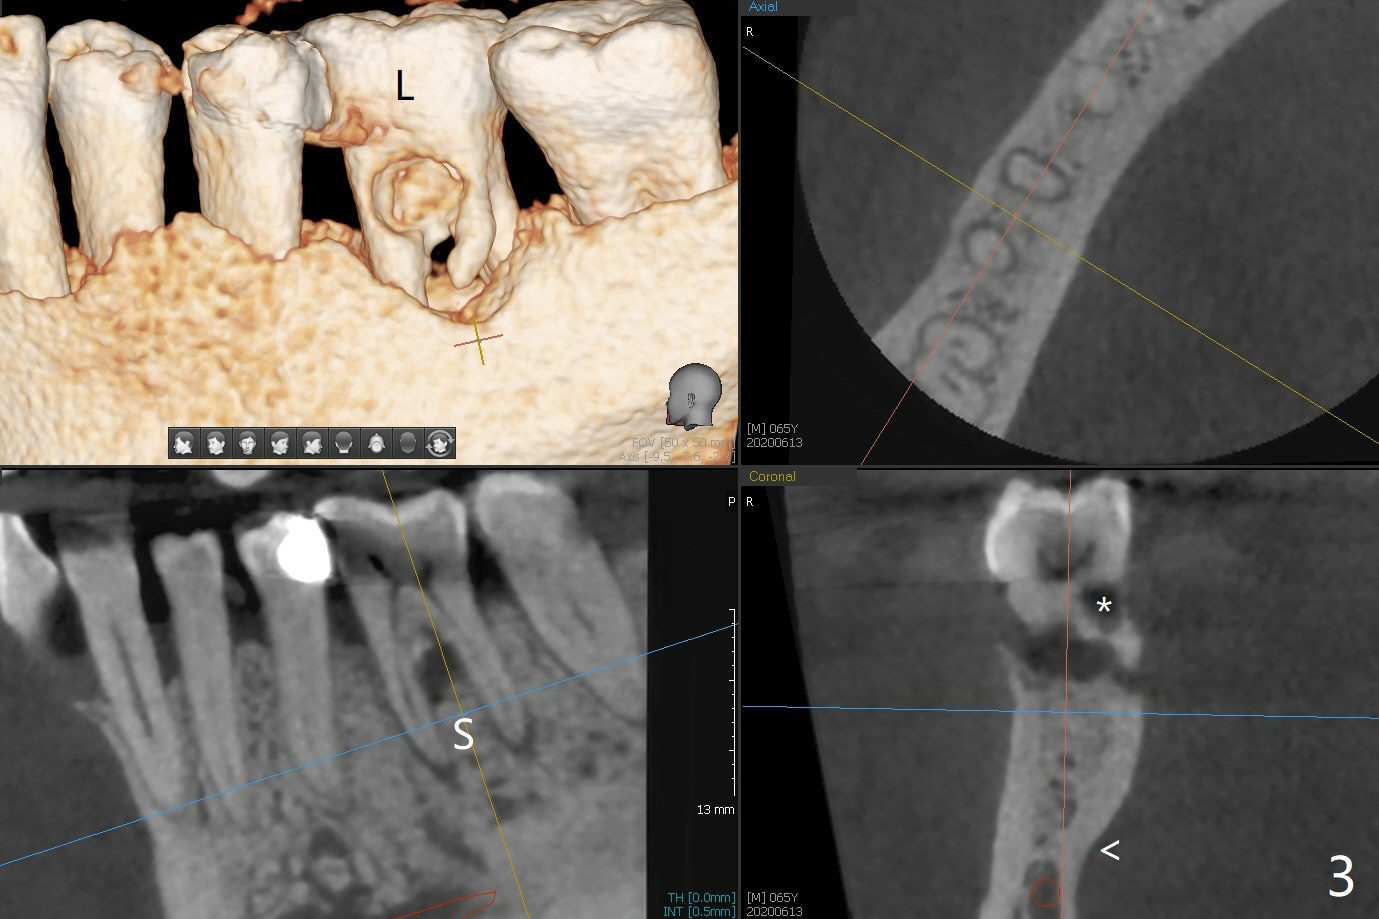

A 65-year-old man has nocturnal pain associated with #30 lingual furca caries and gingival recession (Fig.1,2). PRF (x2) and sticky bone will be used to repair the lingual soft and hard tissue defects. CT shows the submandibular fossa (Fig.3 <), dictating a short implant 10 mm, Fig.4). To place the implant in the septum (Fig.3 S), the coronal portion of the tooth is removed (Fig.5 black area) so that the roots are able to keep the osteotomy without deviation (Fig.6 red arrow). It is possible to place the implant in a trajectory mesiodistally (Fig.7 in fact after root extraction (arrows)). To prevent buccolingual deviation, a small implant (4 mm in diameter) is designed so that it will NOT touch the buccal (B in Fig.8) or lingual (L) plates. The bone density of the cortex and medulla is 2000 and 1400 units, respectively. To reduce the chance of implant fracture because of the narrow diameter in function, an implant with Titanium V will be used.